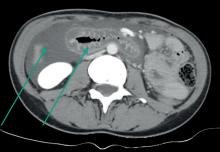

D’après : Doumeizel PM, Robin F, Ballerie A, et al. Effets indésirables de la corticothérapie orale au long cours. Rev Prat 2021;71(6);587-96.